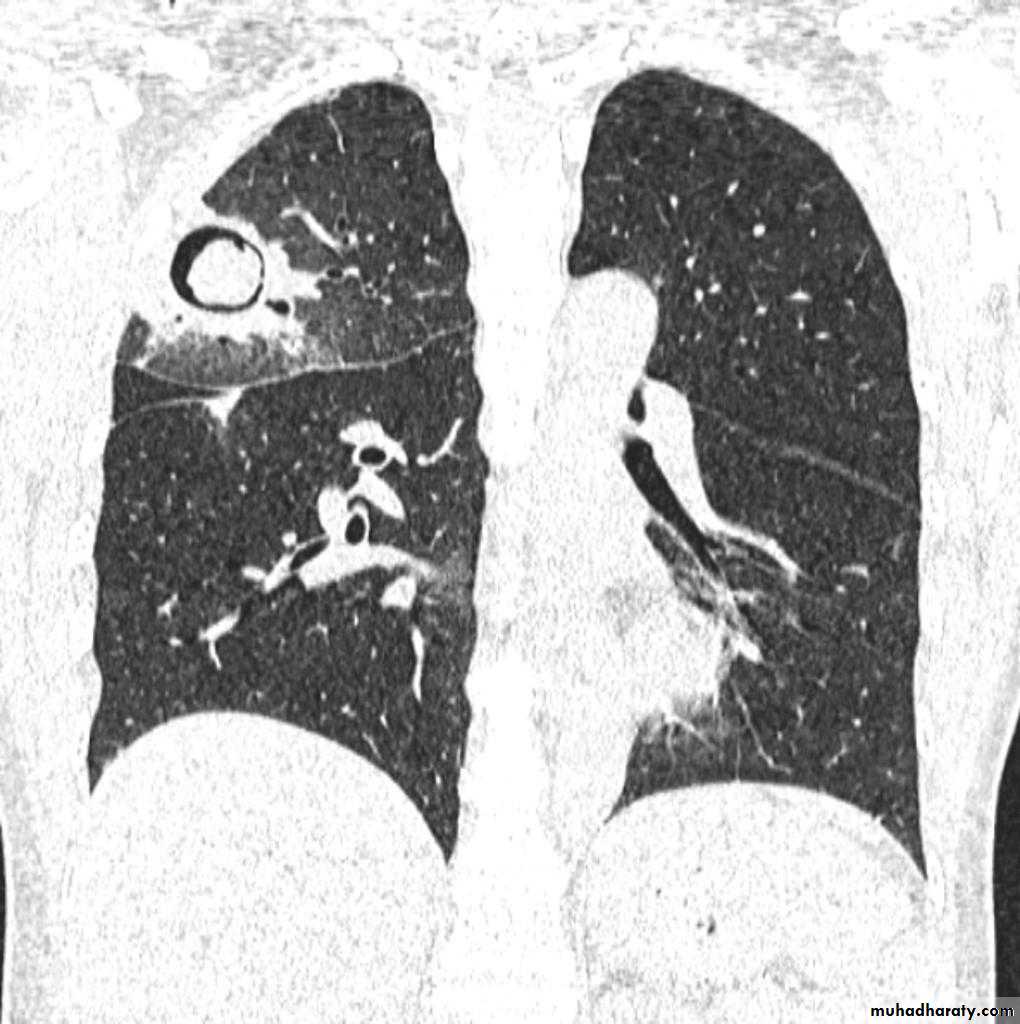

TB lung abscess

67.upper apical TB cavity68.Aspergilloma